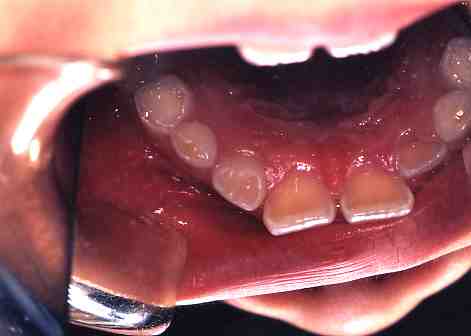

2.術中(ミラー像)

歯科用のスミを塗布して

レーザー照射します。